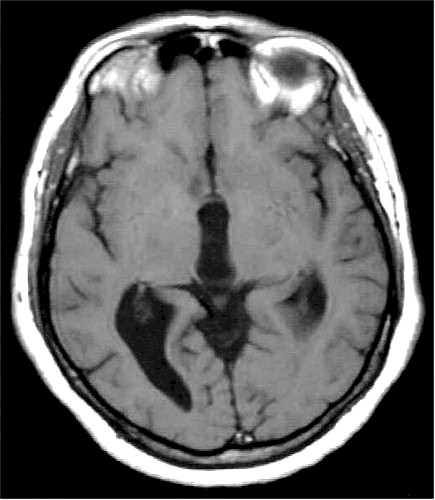

Idrocefalo

"normoteso" alla RM. |

Esito

postventricolocisternostomia. |

Le

indagini neuroradiologiche (TC e RM encefaliche) spesso non mostrano

eclatanti variazioni delle dimensioni ventricolari, pur in presenza di

una scomparsa della sintomatologia. |